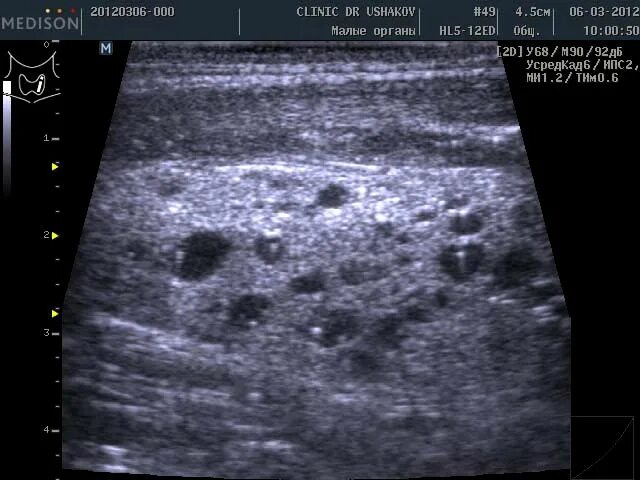

Щитовидная железа диффузные изменения структуры